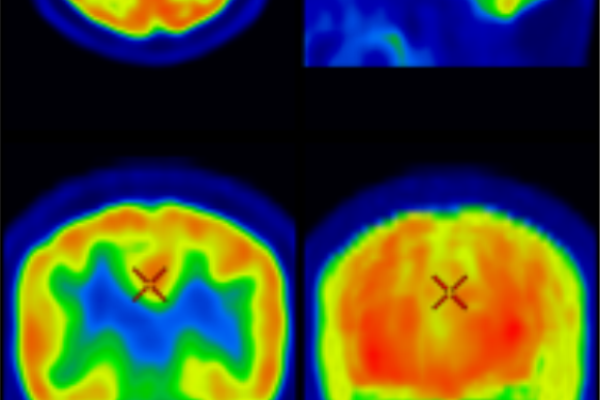

Brain PET

Brain PET imaging is a highly advanced diagnostic tool used to assess the brain’s metabolic activity and function. It plays a crucial role in the early detection and evaluation of neurological conditions such as Alzheimer’s disease, various forms of dementia, epilepsy, and movement disorders like Parkinson’s disease. By analyzing how different areas of the brain process glucose, Brain PET helps distinguish between types of cognitive decline, assess disease progression, and guide treatment planning with greater accuracy than structural imaging alone.

Key Indications:

• Early detection of Alzheimer’s disease and other dementias

• Evaluation of movement disorders (e.g., Parkinsonism)

• Pre-surgical evaluation of epilepsy

• Assessment of brain tumors or infections